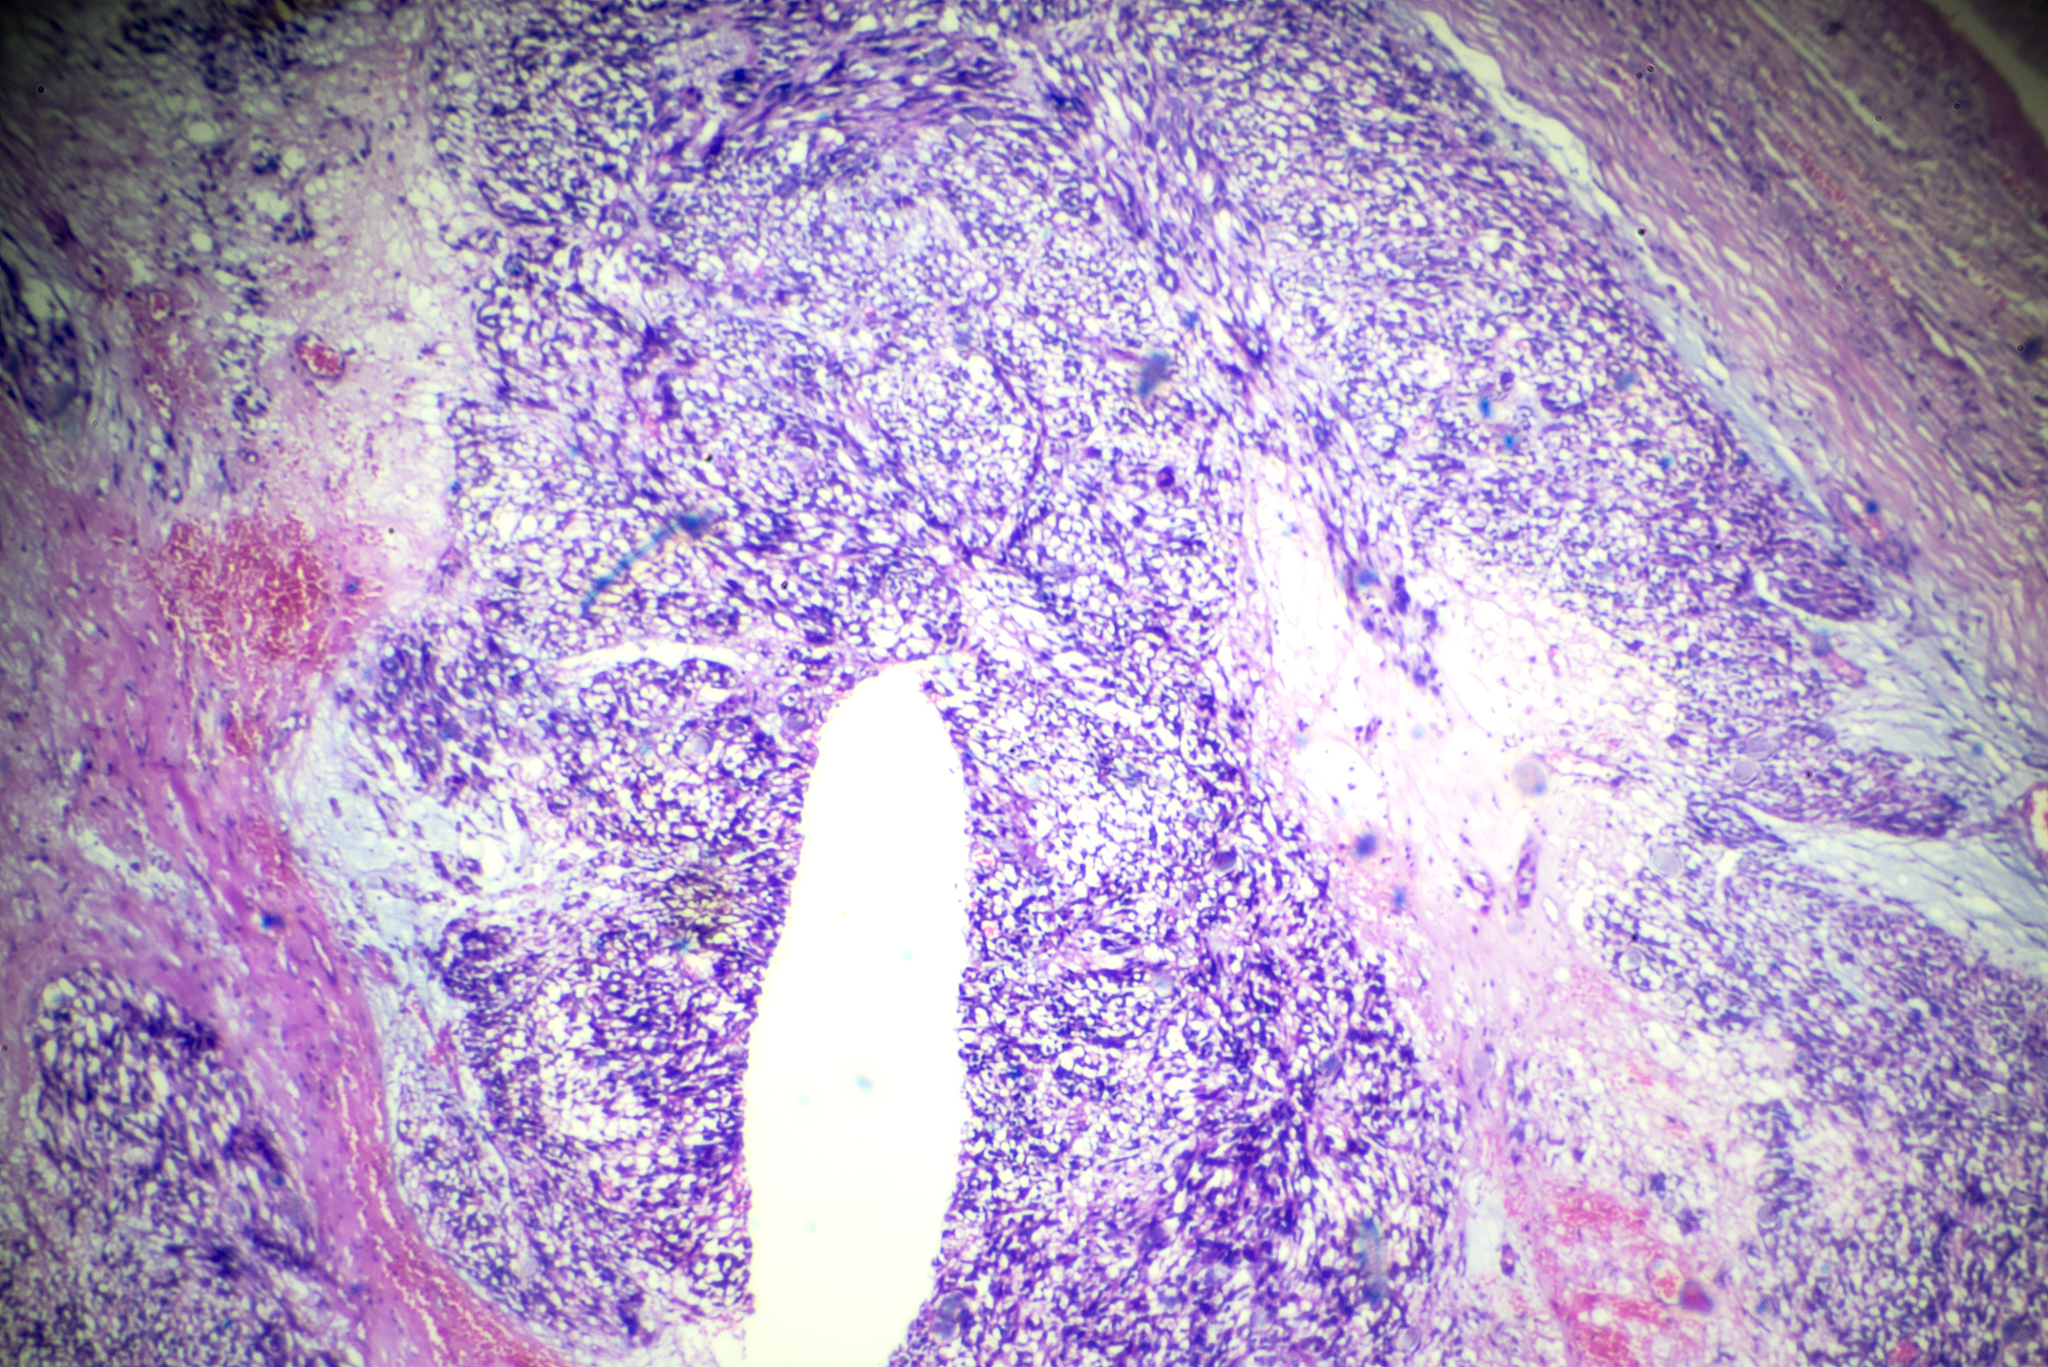

子宫平滑肌瘤是女性常见的良性肿瘤,会对患者的身体和心理健康造成一定影响。专业的护理指导能够帮助患者了解疾病、控制病情,并积极应对治疗带来的挑战。